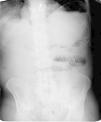

Caso 1: mujer de 85 años, intervenida 40 años antes de colecistectomía como único antecedente personal de interés, que acudió al servicio de urgencias por dolor abdominal tipo cólico, difuso, no irradiado, asociado a vómitos bilioentéricos y ausencia de deposición de 3 días de evolución. En la exploración física destacaba un abdomen duro, distendido, doloroso a la palpación en el hipogastrio, sin peritonismo y ruidos hidroaéreos disminuidos. En la analítica sanguínea destacaban 16.000leucocitos/mm3 con neutrofilia y proteína C reactiva (PCR) mayor de 250mg/l. Una radiografía simple de abdomen mostraba dilatación de las asas del intestino delgado (fig. 1). Ante el diagnóstico de sospecha de suboclusión intestinal secundaria a bridas de la cirugía abdominal previa, se instauró inicialmente tratamiento conservador con reposo intestinal, sueroterapia y colocación de sonda nasogástrica. La paciente no mostró mejoría clínica en las siguientes 48h y el dolor abdominal aumentó, por lo que se realizó una laparotomía exploradora, mediante la que se observó un plastrón inflamatorio en el hipogastrio, incluidas las asas del intestino delgado, adyacentes a un apéndice cecal inflamado, indicativo de apendicitis aguda con una perforación contenida. Se liberaron las asas intestinales incluidas en el plastrón y se realizó una apendicectomía. El postoperatorio transcurrió sin incidencias y se le dio el alta al 6.o día de la intervención. El estudio anatomopatológico mostró una diverticulitis apendicular aguda perforada.